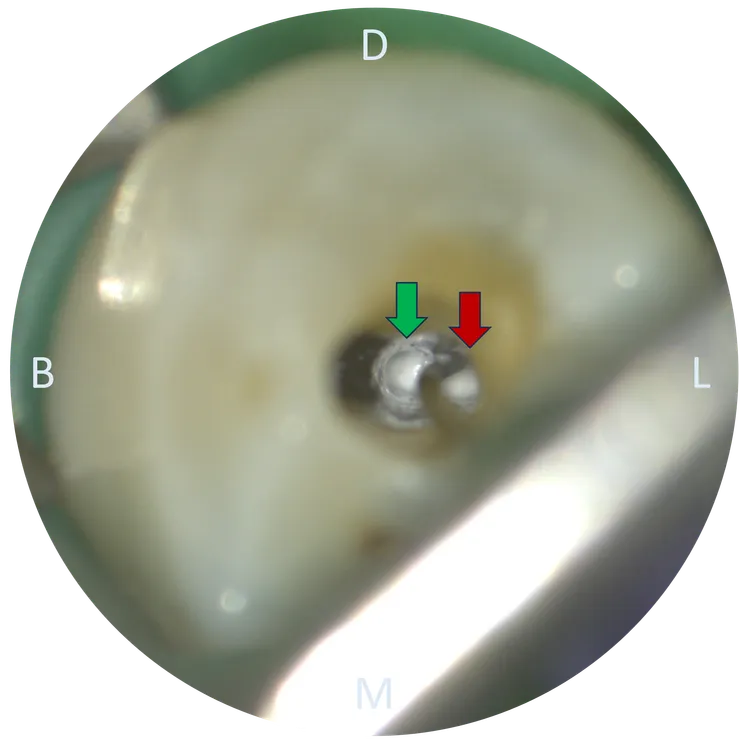

打開之後可以看到,紅色箭頭所指的亮點是轉診醫師找到的 buccal canal.

從 access cavity 的型態看得出來轉診醫師有試著去尋找 lingual canal. 但要找到 h 形的分岔是相當困難的!然後更困難的是找到之後的 C&S......

綠色箭頭所指的白洞是 buccal canal.

紅色箭頭所指的是 #10 C-pilot 彎進 lingual canal 的樣子。